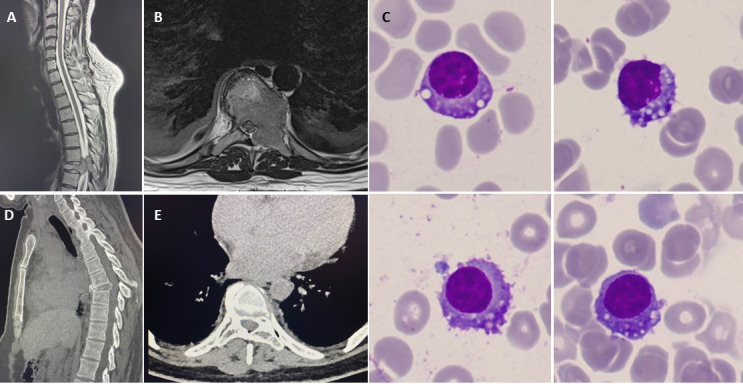

Management of multiple myeloma presenting as malignant spinal cord compression during pregnancy: a case report.

Abstract Image